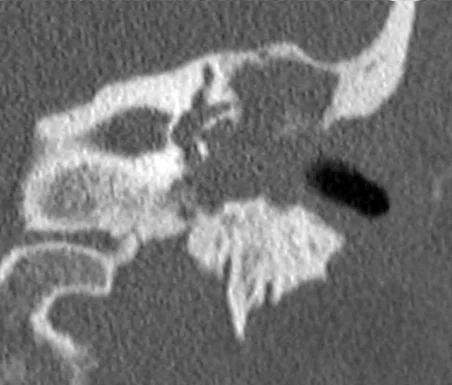

Complicaciones

• Fístula laberíntica: constituye la complicación más frecuente y se produce cuando la erosión ósea avanza hacia el laberinto posterior creando una fístula entre el oído medio y el espacio perilinfático, siendo el lugar más frecuente de comunicación el canal semicircular externo. Esta complicación es importante tenerla en cuenta a la hora de adaptar un audífono, ya que al ejercer presión u oclusión del conducto auditivo externo se pueden desencadenar los síntomas de vértigo debido a la fístula.

Lesión de partes blandas que erosiona el canal semicircular lateral.

• Parálisis facial: debida a la erosión ósea del conducto de Falopio, estuche óseo que protege al facial en el oído medio.

• Hipoacusia neurosensorial: debido a la extensión del colesteatoma al oído interno, produciendo una invasión mecánica o una laberintitis química que puede dañar las células ciliadas.

• Trombosis del seno sigmoides, que es una circunvalación que hace la vena yugular interna en la pared posterior de la cavidad mastoidea y que puede verse afectada por el colesteatoma y progresar hacia el torrente sanguíneo o a la cavidad craneal, provocando complicaciones fatales.

• Rotura del tegmen tímpani, que como hemos descrito anteriormente es la pared ósea que separa el oído medio de la fosa craneal media. Su erosión y rotura puede provocar meningitis y abscesos cerebrales de evolución mortal en ocasiones.